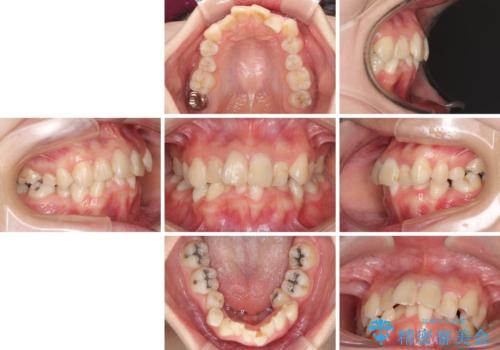

デコボコと深い咬み合わせ ワイヤー装置での抜歯矯正

- 内側に倒れ込んだ歯や下の前歯が隠れてしまうほどの咬み合わせを改善したいとのことで来院された患者様です。

下顎の叢生を解消するために抜歯が必要であり、奥歯の咬み合わせや口元の印象から、上顎も同様に抜歯と判断し、上下左右の第1小臼歯4本抜歯してワイヤー装置にて矯正治療を行うこととしました。

咬み合わせが深く、そのままでは上顎の抜歯スペースが閉じきらない可能性があったため、治療初期から深い咬み合わせを改善させるように試みました。

実際にはなかなか改善されず、当初予定よりも治療期間がやや長期化してしまいました。